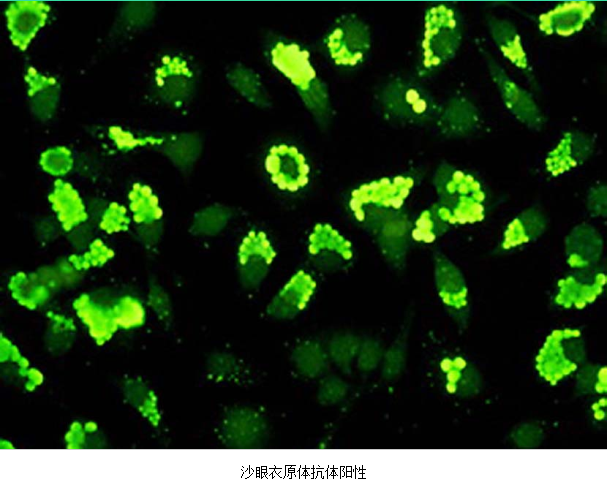

3.病原体检测 应作衣原体及淋病奈瑟菌的检测,以及有无细菌性阴道病及滴虫阴道炎。检测淋病奈瑟菌常用的方法有:①分泌物涂片革兰染色,查找中性粒细胞内有无革兰阴性双球菌,由于子宫颈分泌物的敏感性、特异性差,不推荐用于女性淋病的诊断方法。②淋病奈瑟菌培养,为诊断淋病的金标准方法。③核酸检测,包括核酸杂交及核酸扩增,尤其核酸扩增方法诊断淋病奈瑟菌感染的敏感性及特异性高。检测沙眼衣原体常用的方法有:①衣原体培养,因其方法复杂,临床少用。②酶联免疫吸附试验检测沙眼衣原体抗原,为临床常用的方法。③核酸检测,包括核酸杂交及核酸扩增,尤以后者为检测衣原体感染敏感、特异的方法。但应做好质量控制,避免污染。